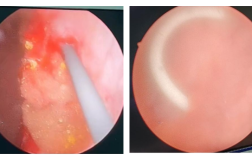

命悬一线,多科联手终力挽狂澜!我院成功救治特重型颅脑损伤、双瞳散大脑疝患者

患者孙某某因车祸致颅脑外伤意识不清1小时后送至我院急诊科。入院时患者已呈昏迷状态,急诊CT提示右侧额颞顶枕部急性硬膜下血肿、广泛脑挫裂伤、蛛网膜下腔出血,中线结构移位明显,大脑镰疝形成,右锁骨骨折,右侧第5肋骨骨折。急诊科董海涛主任医师紧急完善相关术前检查,并请骨科、胸外...